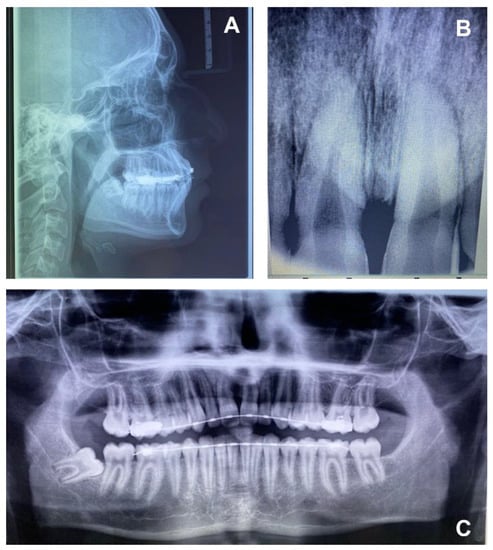

- Intraoral X-rays with periapical and occlusal projections confirm the presence, position and/or anomaly of the retained maxillary incisors and any underlying developmental anomaly or pathology. The buccolingual position of the non-erupted tooth can be localized using horizontal or vertical parallax.

- Ortopanthomography X-ray (OPG X-ray) to evaluate the problem in relation to the entire arch, adjacent tooth and the staging of the eruption of the other dental elements.

- Latero-Lateral Teleradiography (LLT) of the head with cephalometric trace to assess the height and inclination of the crown and root of the impacted tooth.